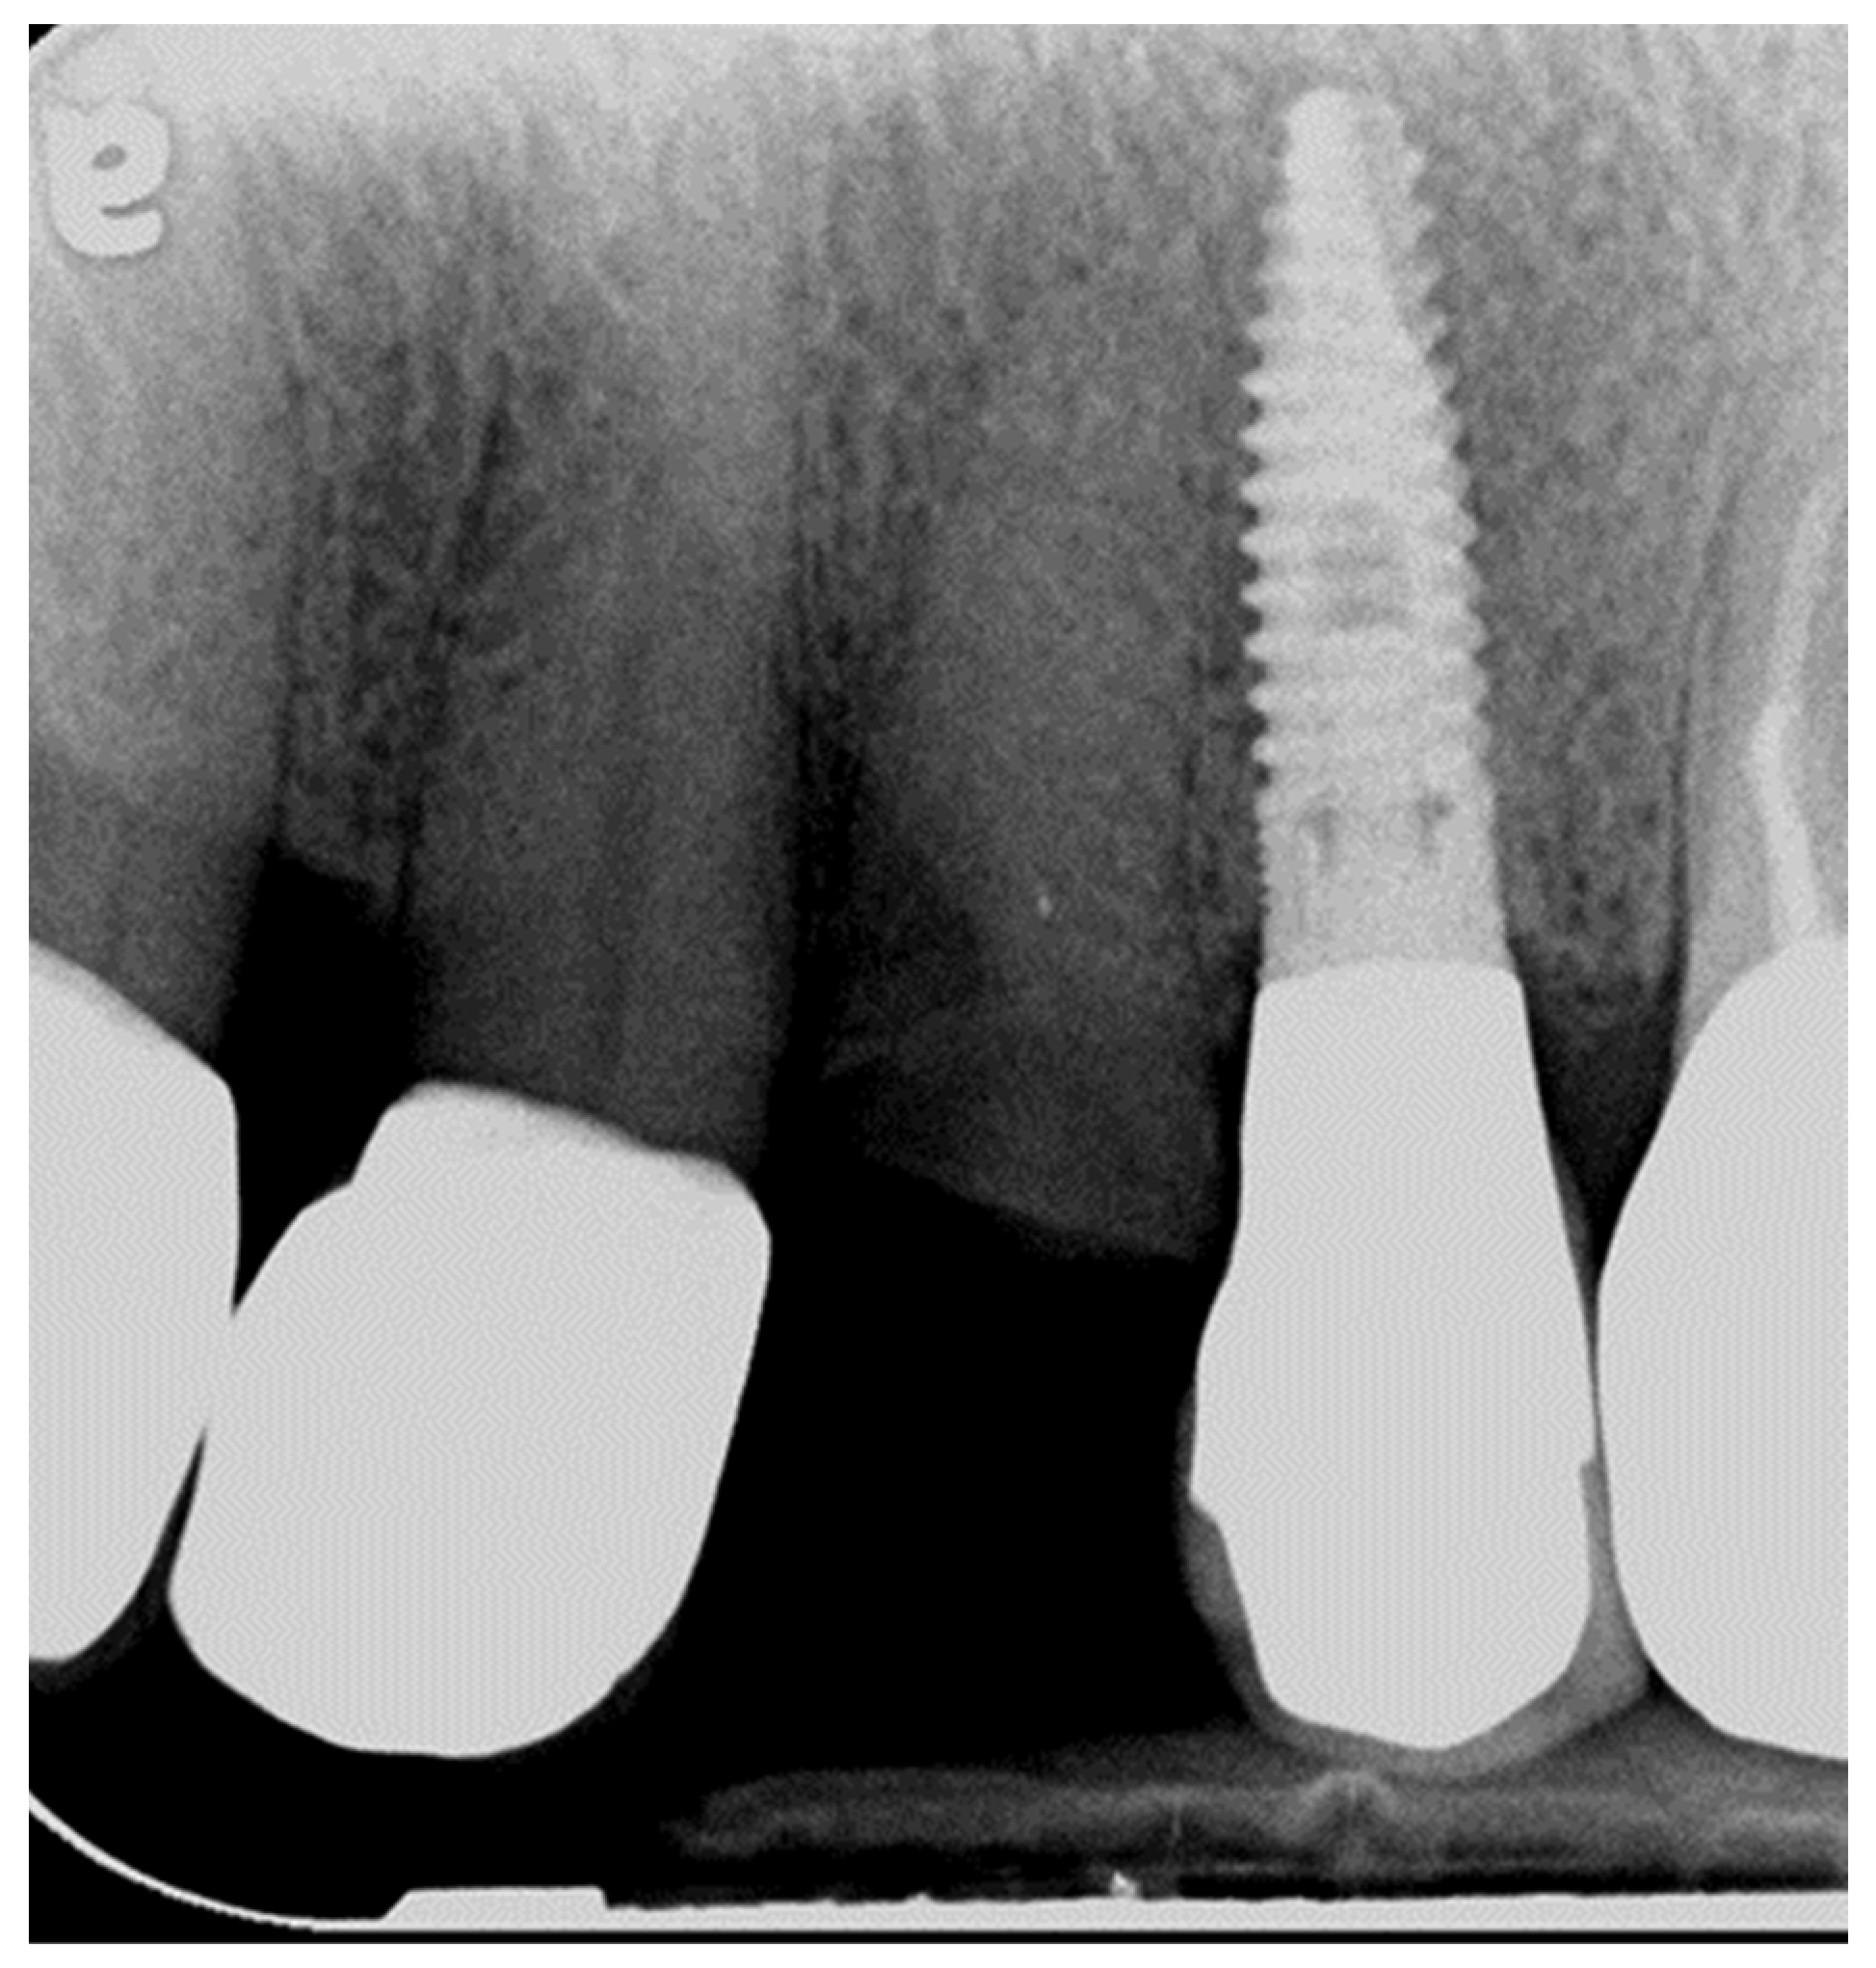

3.1. Biological Findings and Implant Survival Rate